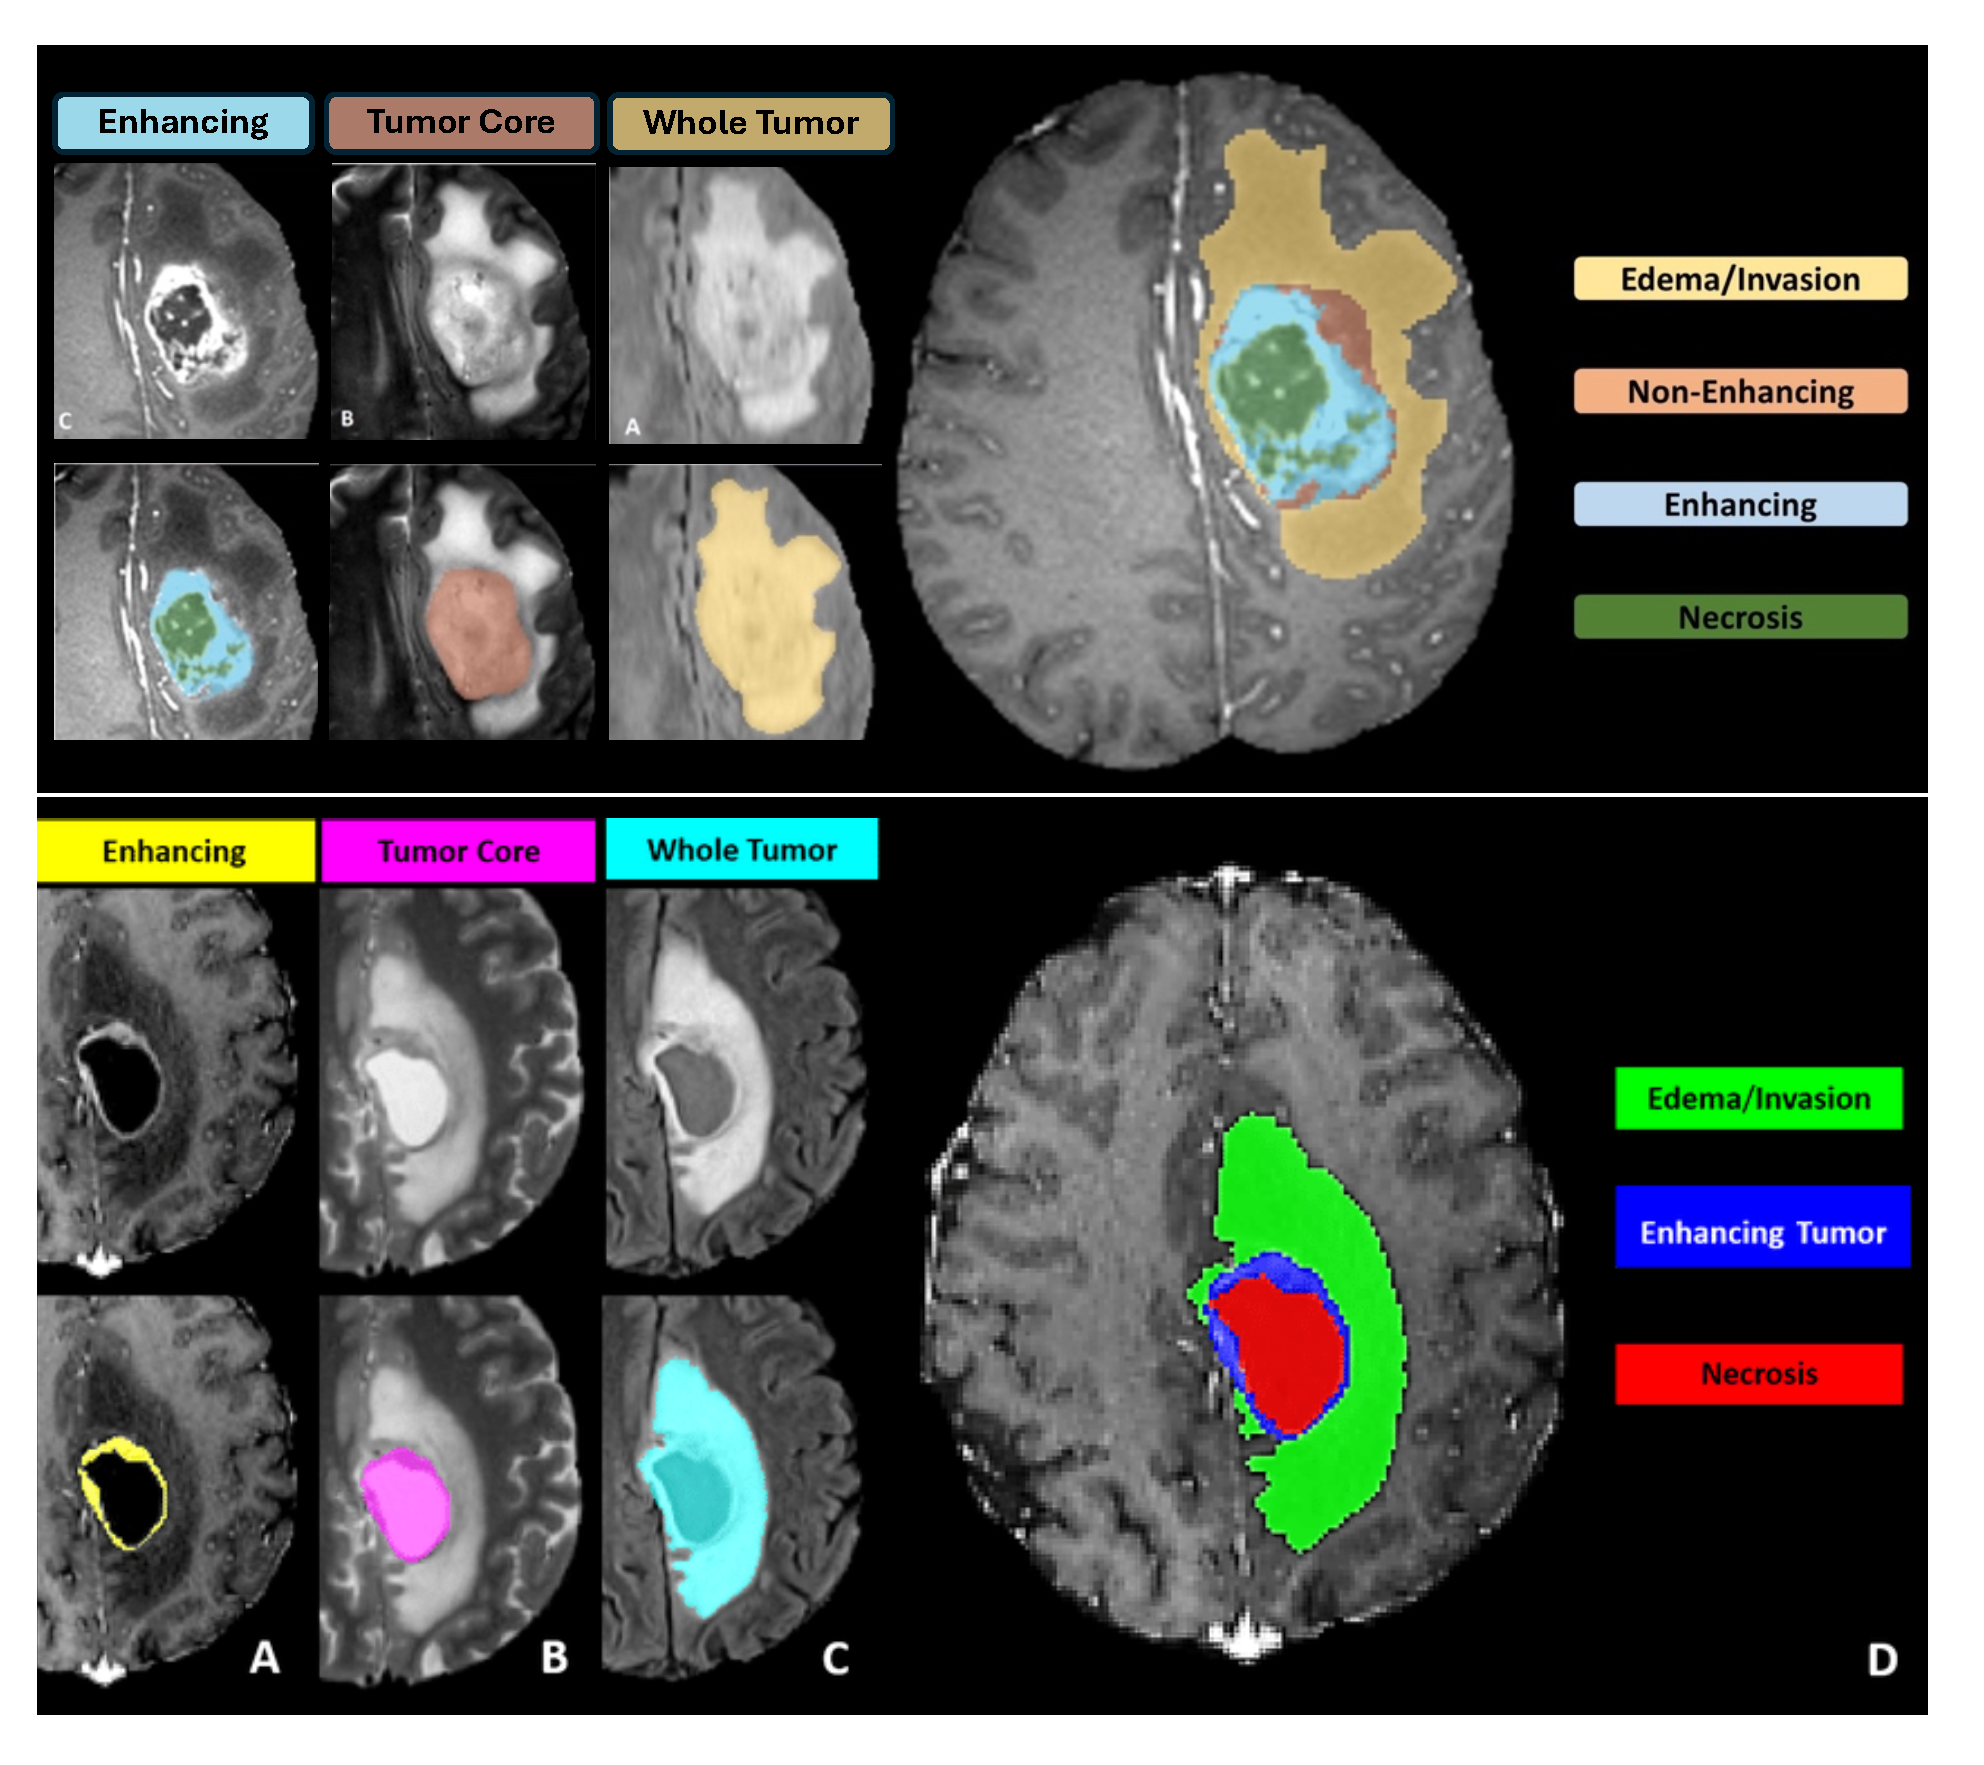

Segmentation - Pediatric Tumors: ASNR-MICCAI BraTS Pediatrics Tumor Challenge: Following pre-processing, the images were segmented into tumor subregions using two pediatric-specific automated deep learning models. These models produced preliminary segmentations of four tumor subregions, as recommended by the Response Assessment in Pediatric Neuro-Oncology (RAPNO) working group for assessing treatment response in high-grade gliomas and DIPGs. The subregions included:- Enhancing tumor (ET): Bright areas on T1 post-contrast images compared to T1 pre-contrast, with mild enhancement verified by comparing normal brain signal intensity.- Cystic component (CC):Very bright on T2 and dark on T1CE, resembling cerebrospinal fluid (CSF) and located within the tumor, either centrally or peripherally.- Non-enhancing tumor (NET): Any abnormal signal within the tumor not classified as enhancing or cystic.- Peritumoral edema (ED): Bright, finger-like areas on FLAIR scans, preserving underlying brain structure and surrounding the tumor.The automated segmentations served as the basis for manual refinement by volunteer neuroradiology experts using ITK-SNAP software. Annotators were provided with all four mpMRI sequences and the fused segmentation volume to guide their corrections. Refined segmentations were then reviewed by three board-certified neuroradiologists. Cases were either approved or returned for additional adjustments in an iterative process until the segmentations were deemed acceptable.For consistency with other BraTS 2023 challenges and to facilitate integration with adult glioma datasets, participants were provided with three final segmentation labels: enhancing tumor (ET); peritumoral edematous area (ED) and non-enhancing component (NC), which is a combination of non-enhancing tumor, cystic component, and necrosis. The comparison between the initial and final labels is shown in Figure v;

Segmentation - Pediatric Tumors: ASNR-MICCAI BraTS Pediatrics Tumor Challenge: Following pre-processing and defacing, a pediatric automated segmentation method was employed to preliminarily segment tumors into four main subregions: enhancing tumor (ET; label 1), non-enhancing tumor (NET; label 2), cystic component (CC; label 3), and peritumoral edema (ED; label 4).The automated segmentation outputs were manually revised by volunteer neuroradiology experts with varying levels of experience, following established annotation guidelines. Refinements were conducted using ITK-SNAP software. Afterward, the refined segmentations were reviewed by three board-certified neuroradiologists. Cases deemed incomplete or inaccurate were returned to the annotators for further adjustments. This iterative review process continued until the segmentations were approved by the neuroradiologists [31]. Note that for the BraTS-PEDs 2024 challenge, the tumor sub-regions considered for evaluation returned to the original four, as initially planned for the BraTS-PEDs 2023 challenge but not implemented that year (see left image in Figure v);